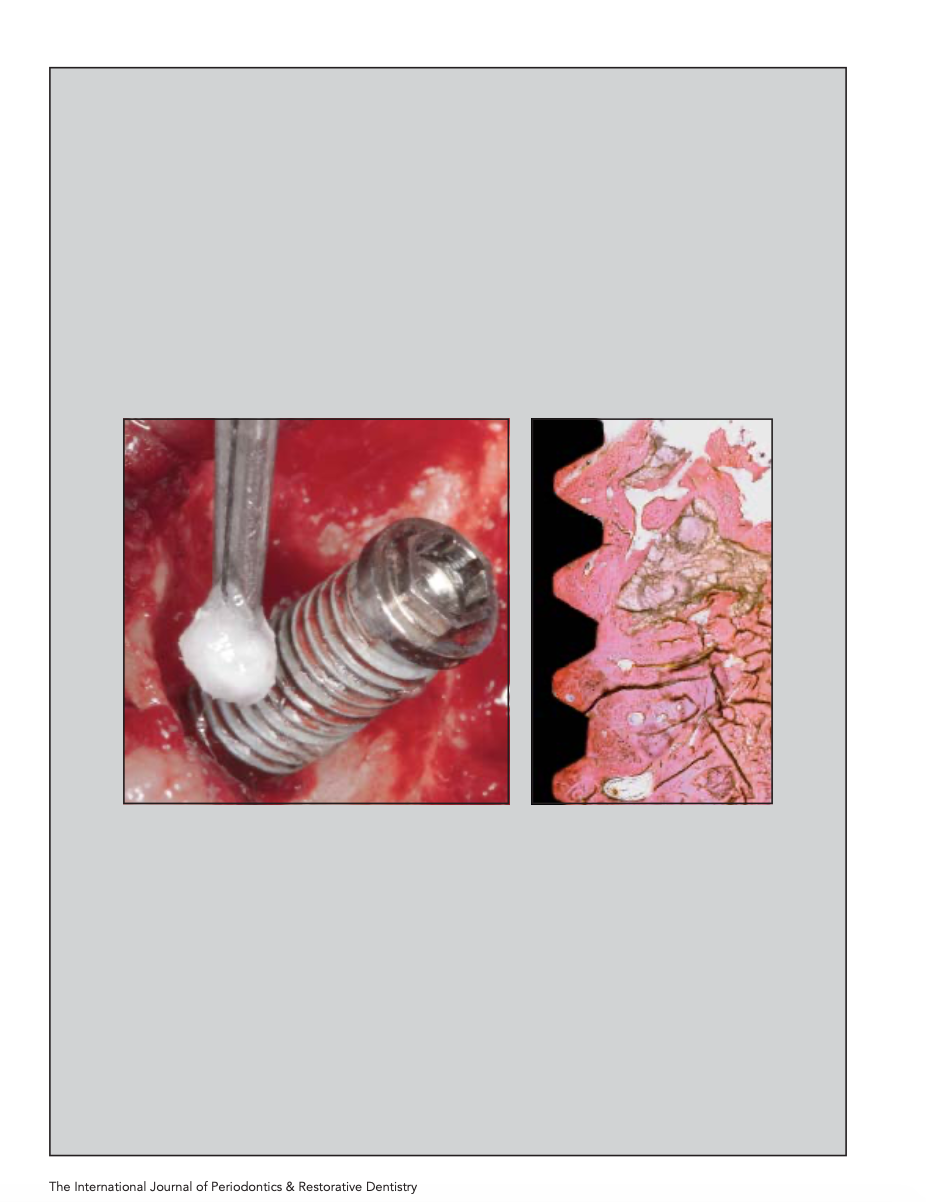

Clinical Considerations: Two patients of 33 and 25 years of age both had significant reduction in the height over their implants in the #7 and #10 locations. The first patient had the implants placed 15 years ago and the second patient had them done 5 years before our treatment. Current techniques to remedy esthetic issues created by malpositioned implants consist of soft and/or hard tissue grafting but tend to be utilized independently of each other in discrete procedures as opposed to being combined in one surgical protocol. The Triple Layer Graft (TLG) surgical protocol is novel in that it incorporates all three layers of grafting to ad- dress both soft and hard tissue deficits in one procedure done at one time after doing a decoronation technique. The TLG surgical and prosthetic protocol has been previously published by these authors, but this article will discuss the rationale along with the technique and indications and contraindications, illustrated via case reports. The authors will also report on the long-term results of this technique.

Conclusions: The Triple Layer Graft TLG) in combination with the Decoronation technique is an effective method in managing mild as well as severe esthetic defects over the facial of previously placed implants.